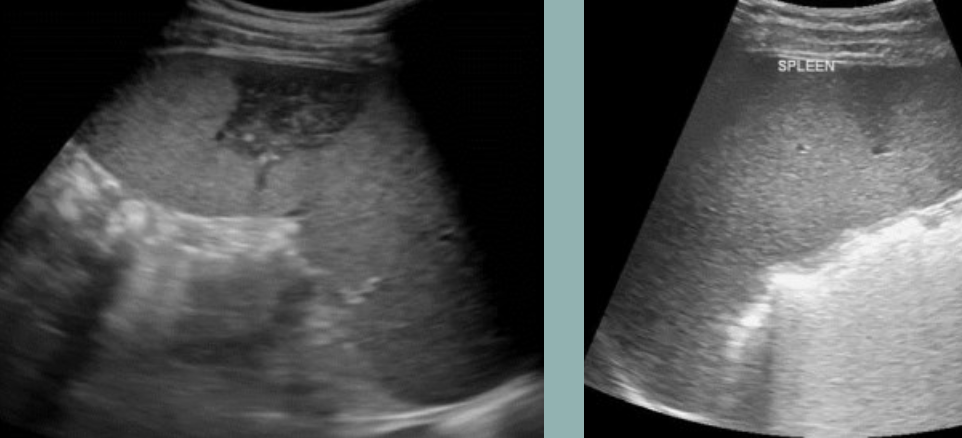

Splenic Trauma → blunt trauma usually resulting in hematoma

clinical hx: usually blunt abdominal trauma, underlying splenomegaly increased risk

s/sx: LUQ pain, low hematocrit from bleeding, abdominal swelling/bloating discomfort

2D US: capsule intact = subcapsular hematoma (conforms to spleen shape), ruptured capsule = free fluid/hematoma may form (check abdominal gutters for free fluid)

color doppler: avascular

DDX: splenic infarction, splenic abscess